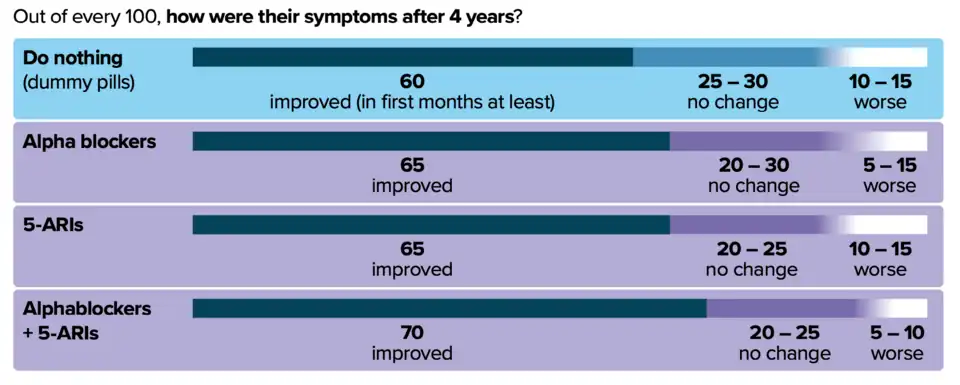

Medications

The two main medication classes for BPH management are alpha blockers and 5α-reductase inhibitors.[64]

Alpha-blockers

Selective α1-blockers are the most common choice for initial therapy.[65][66][67] They include alfuzosin,[68][69] doxazosin,[70] silodosin, tamsulosin, terazosin, and naftopidil.[58] They have a small to moderate benefit at improving symptoms.[71][58][72] Selective alpha-1 blockers are similar in effectiveness but have slightly different side effect profiles.[71][58][72] Alpha blockers relax smooth muscle in the prostate and the bladder neck, thus decreasing the blockage of urine flow. Common side effects of alpha-blockers include orthostatic hypotension (a head rush or dizzy spell when standing up or stretching), ejaculation changes, erectile dysfunction,[73] headaches, nasal congestion, and weakness. For men with LUTS due to an enlarged prostate, the effects of naftopidil, tamsulosin, and silodosin on urinary symptoms and quality of life may be similar.[58] Naftopidil and tamsulosin may have similar levels of unwanted sexual side effects but fewer unwanted side effects than silodosin.[58]

5α-reductase inhibitors

The 5α-reductase inhibitors finasteride and dutasteride may also be used in people with BPH.[75] These medications inhibit the 5α-reductase enzyme, which, in turn, inhibits the production of DHT, a hormone responsible for enlarging the prostate. Effects may take longer to appear than alpha blockers, but they persist for many years.[76] When used together with alpha-blockers, no benefit was reported in short-term trials, but in a longer-term study (3–4 years) there was a greater reduction in BPH progression to acute urinary retention and surgery than with either agent alone, especially in people with more severe symptoms and larger prostates.[77][78][79] Other trials have confirmed reductions in symptoms, within 6 months in one trial, an effect that was maintained after withdrawal of the alpha blocker.[78][80] Side effects include decreased libido and ejaculatory or erectile dysfunction.[81][82] The 5α-reductase inhibitors are contraindicated in pregnant women because of their teratogenicity due to interference with fetal testosterone metabolism, and as a precaution, pregnant women should not handle crushed or broken tablets.[83]